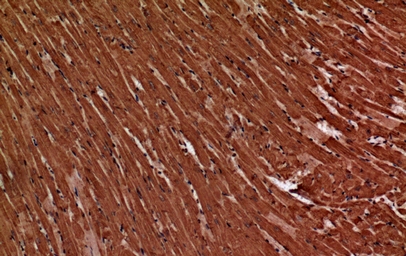

IHC (Immunohistochemisry)

(Immunochemical staining of human Troponin C in human heart with rabbit polyclonal antibody at 1:500 dilution, formalin-fixed paraffin embedded sections.)